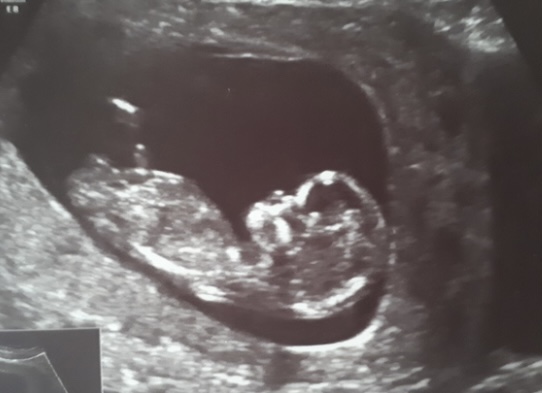

Работы до фига, естественно никто не знает о беременности, на учёт не встала, НО все анализы сдала, узи сделала - все вроде пока норм. Всё из выше перечисленного делала платно.

Вопрос. На 1 скрининг, отправляет только гинеколог после постановки на учёт, платно никто не делает! На учёт планирую встать не ранее 15 недели (есть причины).

Беременяшки, говорят, что могут быть проблемы потом с постановкой на учёт, если нет 1 скрининга, так ли это? С предыдущими беременностями мне его вообще не назначали и всё хорошо, а сейчас видимо всё поменялось 🙄 кто сталкивался с данным вопросом? Так ли необходим 1 скрининг. ( для чего он нужен я знаю, рожать всё равно буду 🤗).